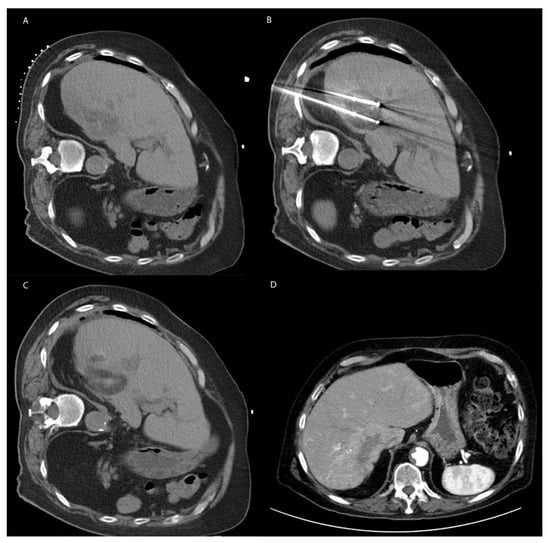

8.1. Technique

8.2. Irreversible Electroporation in Non-HCC Primary Liver Malignancy and Metastatic Disease to the Liver